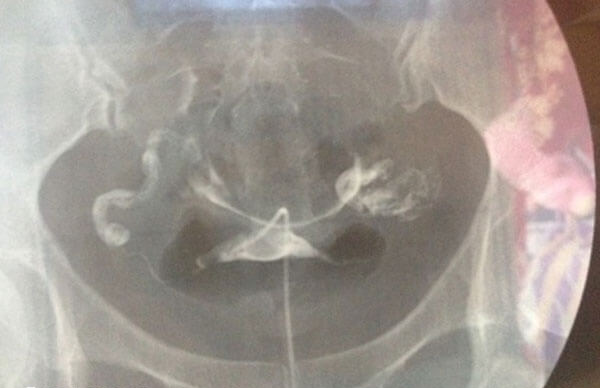

若发现输卵管增粗影,建议及时咨询生殖科医生,通过输卵管造影、超声等检查明确病因。对于积水或严重炎症,通常建议在胚胎移植前进行处理(如输卵管切除、栓塞等),以提高移植成功率。